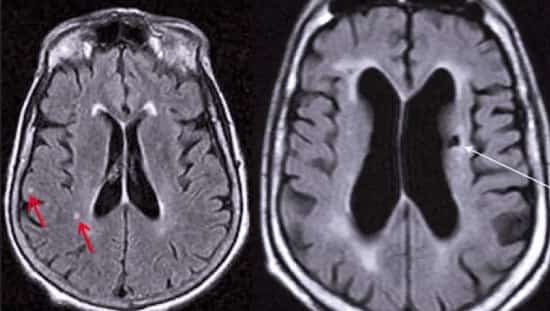

«Тихий» инсульт — закупоривание сосудов головного мозга в результате образования тромба и нарушение кровоснабжения его отдельных участков, но, в отличие от обычного инсульта, незаметное для человека. Однако, несмотря на свою «незаметность», он в любом случае инициирует процессы, приводящие к нарушению функций мозга вплоть до слабоумия.

Тихий инсульт:Среди жертв «тихого» инсульта 84% получили одно повреждение мозга, оставшиеся — более одного.